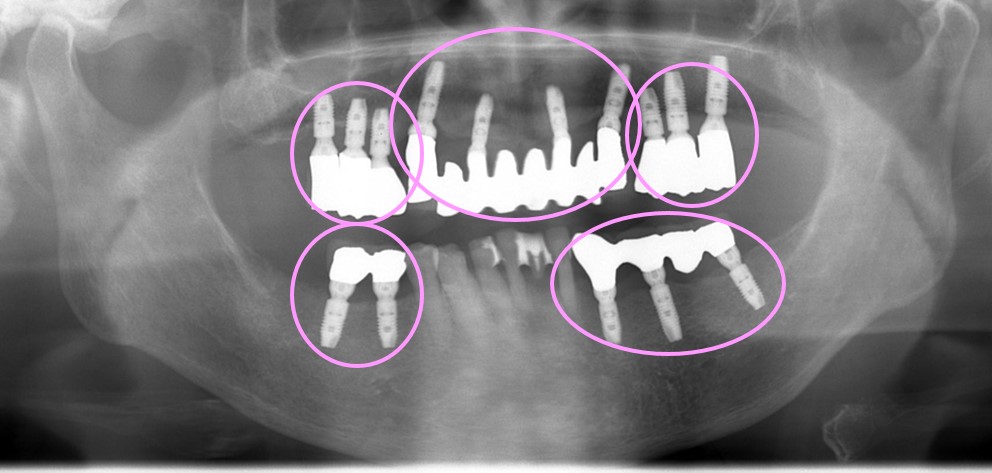

上顎は総入れ歯を使用していただいて、その間にインプラントを順番に埋入していく計画としました。下のレントゲン写真ではピンクの〇で囲った部分が5つありますが、5回に分けてインプラントを埋入していきました。

術後の口腔内写真です。インプラントは数年かけて合計15本埋入されました。土台の金属部分が見えますが問題ありません。メインテナンスを行いやすい設計になっています。